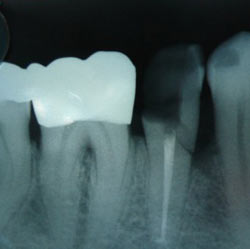

An X-ray of a molar root filling, showing the white lines inside the roots of the toothmolar root filling

In the image above, there is a small amount of filling paste extruded out of the tip of each root. It is the little white blob on each root tip.